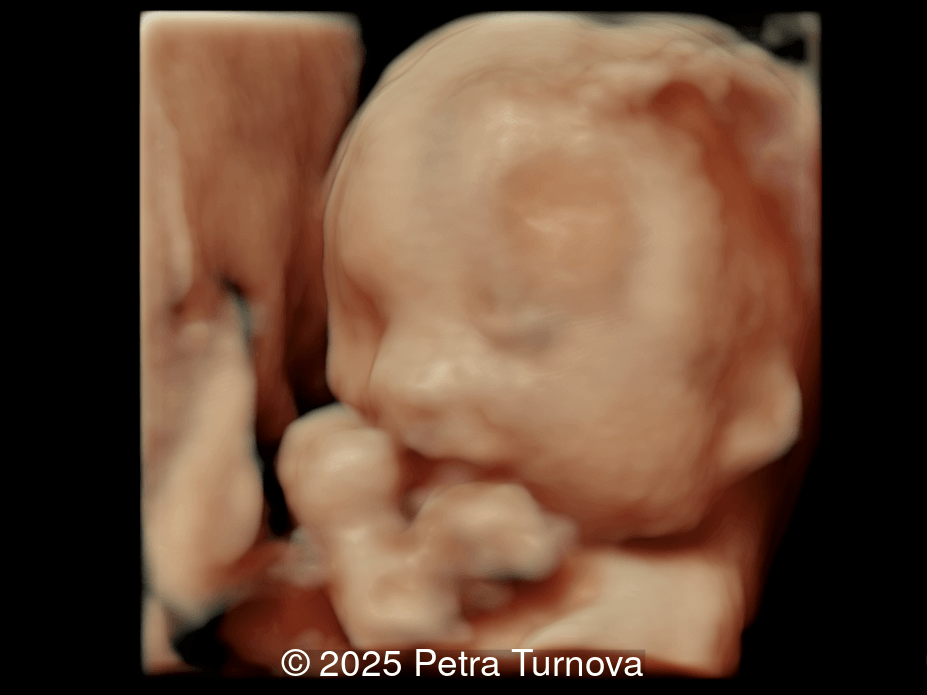

Our imaging revealed malformations in all four limbs with elbow, wrist, and knee joints fixed in extension, as well as foot and ankle malformations. Profile abnormalities were observed with prefrontal edema, flat profile and retro-micrognathia. Ultrasound demonstrated minimal stomach filling related to a lack of swallowing ability and hypoplastic lungs due to poor diaphragmatic movement. Nuchal edema was present.